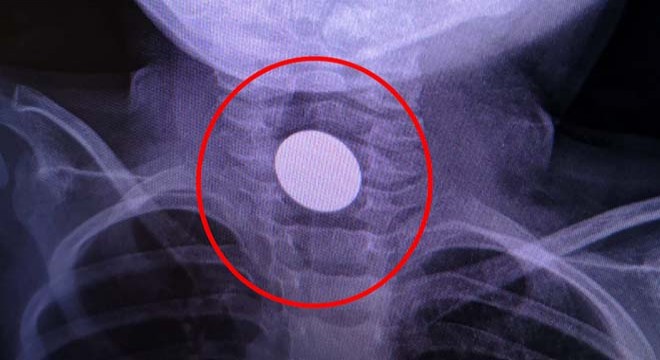

Hamza'nın boğazına takılan 1 lira çıkarıldı

BURSA'nın İnegöl ilçesinde, Hamza K.'nin (3) boğazına takılı kalan madeni 1 lira, hastanede yapılan müdahale ile çıkarıldı.

Bursa'nın İnegöl ilçesi Süleymaniye Mahallesi'nde yaşayan Mevlüt ve Hilal K. çiftinin oğulları Hamza, salonda bulduğu madeni 1 lirayı ağzına attı. Ancak para, çocuğun boğazına takıldı. Hamza hemen İnegöl Devlet Hastanesi'ne götürüldü. Burada yapılan ilk müdahalenin ardından da Dörtçelik Çocuk Hastanesi'ne sevk edildi.

Para, yapılan operasyon ile çıkarıldı. Çocuğun sağlık durumunun iyi olduğu öğrenildi.

BURSA'NIN INEGOL ILCESINDE BOGAZINA MADENI 1 LIRA TAKILAN 3 YASINDAKI HAMZA K. TEDAVIYE ALINDI.FOTO:BURSA-DHA